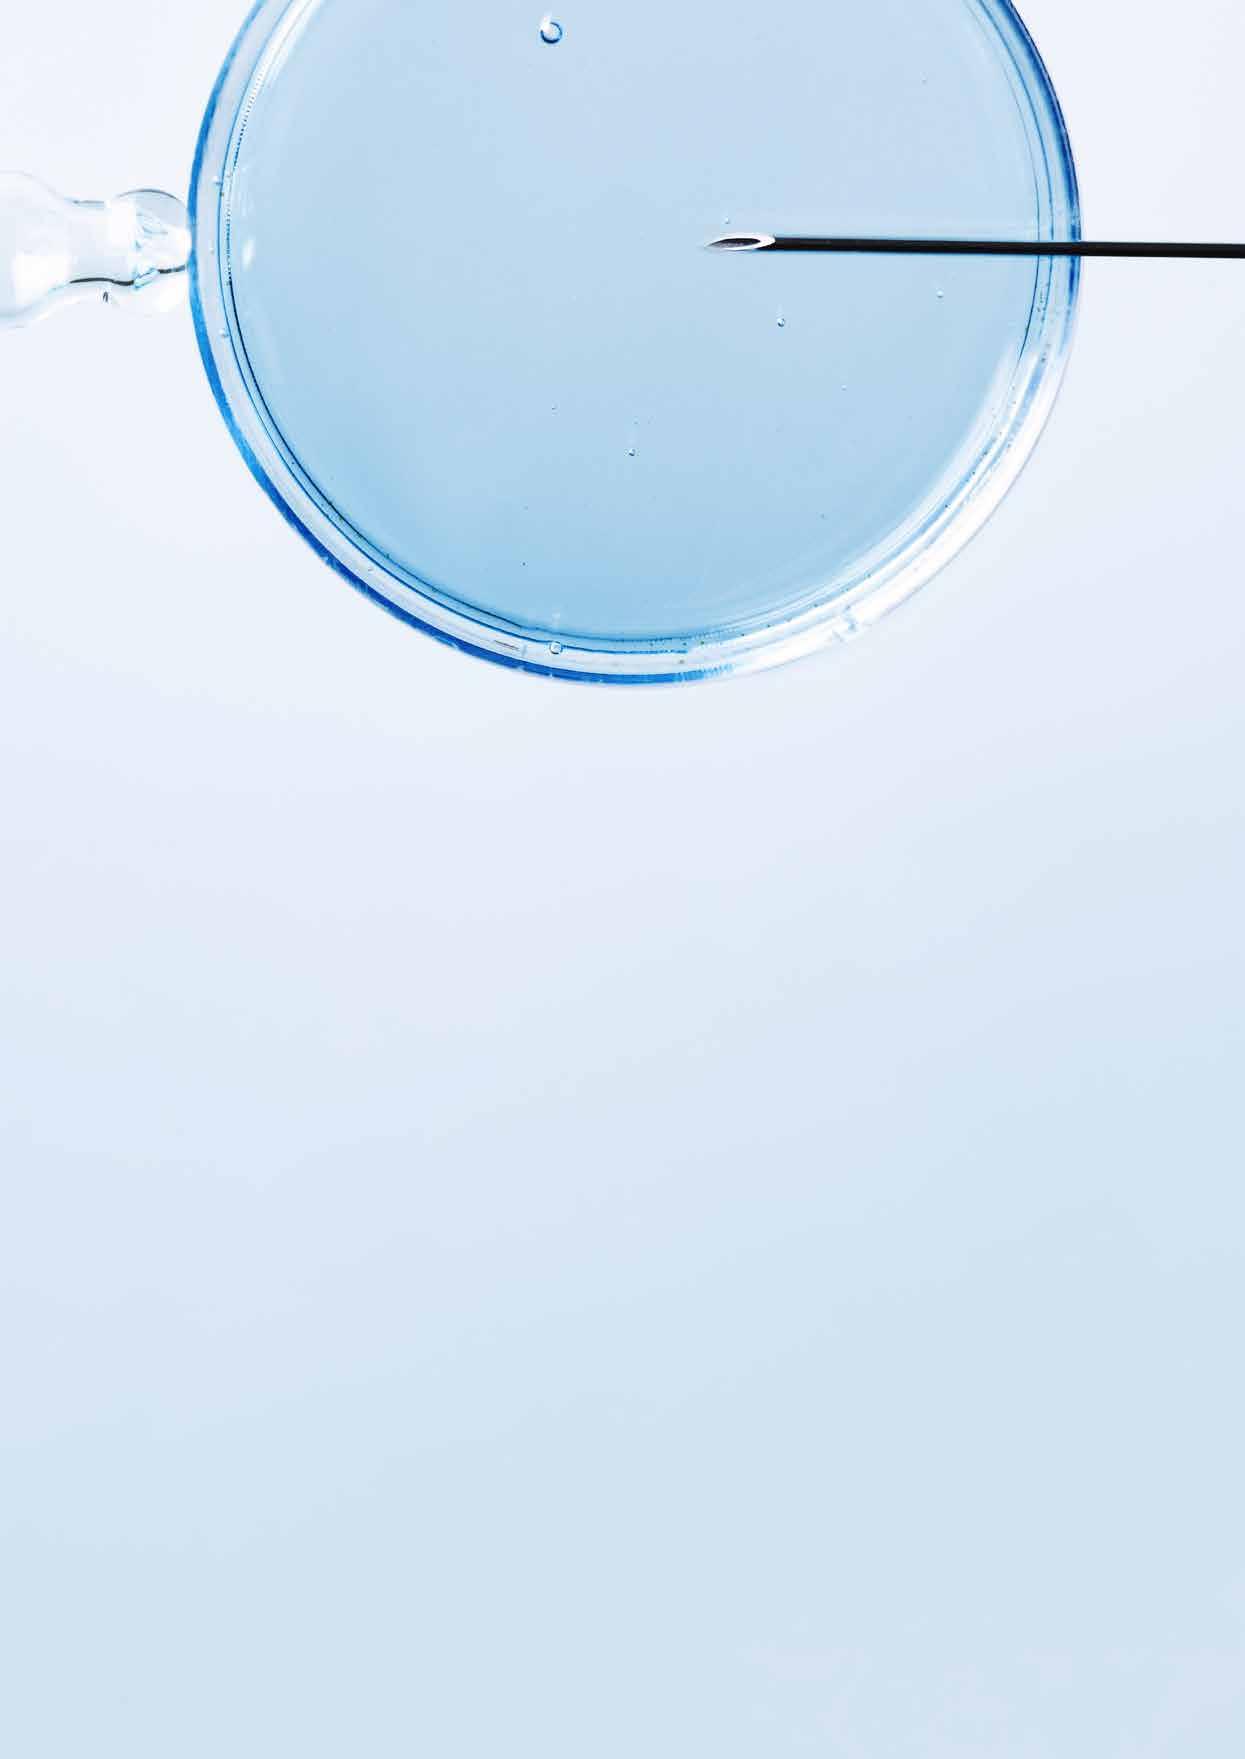

«Viele Paare gehen davon aus, dass eine künstliche Befruchtung in jedem Fall klappt – dem ist leider nicht so», sagt Gabriele Rauscher. Eine häufige Methode, die am Kinderwunschzentrum Baden jährlich Hunderte Male angewendet wird, ist jene der intrauterinen Insemination. Bei dieser Behandlung führt die Ärztin aufbereitete Spermien mithilfe eines Katheterschlauchs direkt in die Gebärmutterhöhle der Frau ein. Die Geburtenrate beträgt dabei zehn bis zwölf Prozent.

Mehr Aufwand, grössere Erfolgschancen

Bei der intrazytoplasmatischen Spermieninjektion und der In-Vitro-Fertilisation liegt die Erfolgschance bei maximal vierzig Prozent. Dafür ist auch der Aufwand grösser. Dazu werden der Frau zuerst eine oder mehrere Eizellen entnommen. «Dabei führe ich eine Nadel durch die Wand der Scheide in den Eierstock ein, um dort die Eizellen abzusaugen», sagt Gabriele Rauscher. «Danach befruchten unsere Biologen die Eizelle mit dem Spermium.» Den im Brutkasten herangereiften Embryo setzt die Ärztin nach einigen Tagen wieder in die Gebärmutter ein. «Dieser Prozess und die Wartezeit sind für die Beteiligten oft sehr belastend. Deshalb sind Aufklärung und psychologischer Support ein wichtiger Teil meiner Arbeit.»

Risiken einer späten Schwangerschaft

Eine künstliche Befruchtung ist stets mit einem operativen Eingriff verbunden, was ein gewisses Risiko mit

sich bringt. Hauptproblem ist allerdings oft das Alter der Eltern. Gabriele Rauscher: «Ab 35 Jahren verschlechtert sich die Chance, schwanger zu werden, rapide. Ausserdem sind späte Schwangerschaften häufig komplikationsträchtiger.» Grundsätzlich ist dank künstlicher Befruchtung vieles möglich. «Aber man sollte den Kinderwunsch nicht unendlich vor sich hinschieben, denn sonst stossen wir an die Grenzen des Machbaren», sagt Gabriele Rauscher.

Gabriele Rauscher ist Fachärztin Reproduktionsmedizin und gynäkologische Endokrinologie am Kinderwunschzentrum Baden.